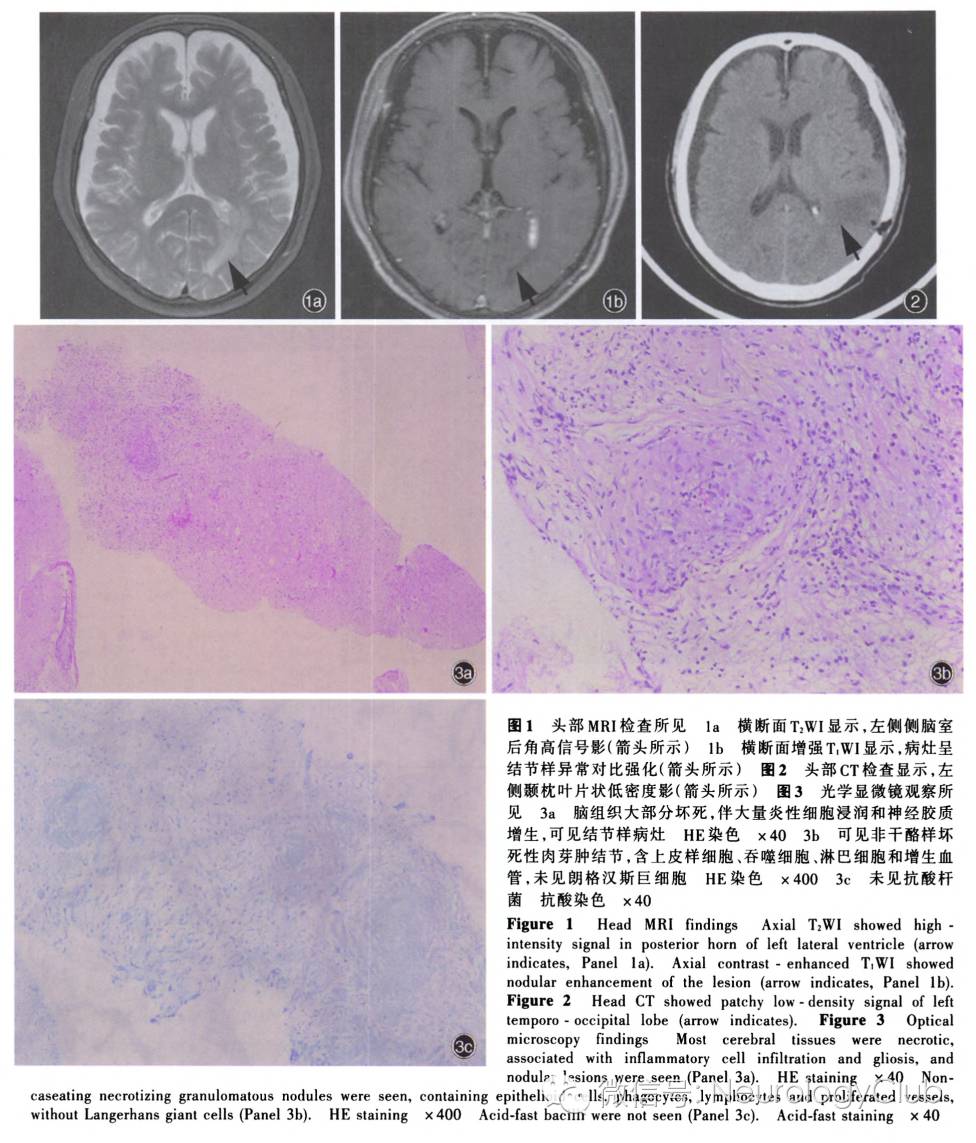

患者男性,69岁,主因行走不稳4个月,双下肢麻木无力、发作性抖动3个月,于2015年11月10日入我院神经科。患者4个月前(2015年7月)无明显诱因出现行走不稳,不自主向左侧歪斜;约1个月后(2015年8月)出现双下肢麻木、无力,行走时前屈、前倾,伴静止时双下肢发作性抖动,动作幅度较大,持续数分钟,2-3次/d,夜间加重、活动或自行按摩后缓解,无头晕、头痛,无意识障碍等。外院头部MRI(2015年9月5日)显示,左侧侧脑室后角和周围占位性病变,伴大面积水肿,增强扫描病变呈结节样强化,考虑脑转移瘤可能性大,不排除分化不良的室管膜瘤等可能;亦可见硬膜下积液,脑白质变性。为求进一步诊断与治疗,于2015年9月14日首次收入我院神经外科,入院后体格检查:右侧颞部视野缺损,左侧额部和耳上皮肤针刺觉减退,左下肢肌力4级、余肢体肌力正常,肌张力均增高,双侧Babinski征阳性。复查头部MRI显示,左侧侧脑室脉络丛、枕角室管膜下占位性病变(图1),不支持高级别神经上皮组织肿瘤;进一步行18F-脱氧葡萄糖18F-FDG)PET显示,左侧侧脑室后角代谢增高。遂于2015年9月23日行立体定向脑深部病变(左侧侧脑室后角)穿刺活检术。患者住院13d,出院等待病理学检查结果,遵医嘱服用丙戊酸钠缓释片(德巴金)0.50g/次(2次/d)、维生素B1 10mg/次(3次/d)以及甲钴胺(弥可保)0.50mg/次(3次/d)。出院后5d(2015年10月1日)突然出现反应迟钝、睡眠增多、言语不能、持筷不能,双下肢无力、行走不稳加重,遂至我院神经外科急诊就诊。头部CT显示,左侧颞枕叶片状低密度影,提示水肿可能(图2),予甲泼尼龙(美卓乐)20mg/d 口服,治疗3d后每3天减量4mg直至停药,共治疗15d,以及甘油果糖氯化钠注射液250ml/次(2次/d)静脉滴注1d后改为甘油合剂50ml/次(2次/d)口服5d。治疗3d后(2015年10月4日)逐渐好转,言语和思维有逻辑,可识家人,继续上述治疗。至2015年10月10日,脑组织活检病理学检查显示,左侧侧脑室后角少许脑组织,并可见类上皮样肉芽肿结节(图3),建议排除结核病等感染性疾病。遂于2015年10月20日至我院感染科门诊就诊,实验室检查血清结核分枝杆菌感染T细胞斑点试验(T-SPOT.TB)和结核分枝杆菌抗体均呈阴性,红细胞沉降率(ESR)和C-反应蛋白(CRP)均于正常值范围,考虑结核病可能性不大。为求进一步诊断与治疗,于2015年11月9日至我院神经科门诊就诊,体格检查:脑神经未见明显异常,双下肢腱反射活跃,双侧Babinski征阳性,步态正常,可直线行走。复查头部MRI显示病灶较前明显缩小(图4)。予氯硝安定1mg/晚口服,双下肢不自主抖动明显缓解,自觉至10月10日行走不稳已较前好转。门诊以“颅内占位性病变,性质待查”收入院。患者自发病以来,否认口干、眼干、皮疹、光过敏、雷诺现象等,精神、睡眠和饮食正常,小便频繁、大便多年依赖通便药物,体重无明显变化。

诊断与治疗经过  经神经科会诊脑组织活检病理学结果,光学显微镜下可见非干酪样类上皮样肉芽肿结节,最终诊断为神经系统结节病。予甲泼尼龙1000mg/d静脉滴注冲击治疗,治疗5d后改为60mg/d口服,每周减量5mg。患者共住院27d,出院时双下肢麻木无力症状缓解,行走不稳好转;双上肢肌力5级、右下肢5-级、左下肢4+级,双足背屈、趾屈5级。出院后1个月(2016年1月4日)至门诊随访,行走不稳好转30%,下肢肌阵挛样抖动发作频率明显减少,体格检查:脑神经未见明显异常,四肢肌力5级、肌张力正常,双侧膝腱反射活跃,双侧Babinski征阳性,步基宽,Romberg征阳性。遂将泼尼松剂量调整为35mg/d口服,嘱患者随访调整药物剂量;1个月后(2016年2月)随访,运动功能无变化,未继续好转,再次将泼尼松增量至40mg/d口服,复查头部和颈胸椎MRI显示,原病灶明显陈旧;2个月后(2016年4月)随访,病情再次好转,可独立从椅子上站起、行走,体格检查:四肢肌力5级,其余无变化,遂将泼尼松剂量减至40mg/d隔日口服;3个月后(2016年7月)随访,出现下肢无力症状加重趋势,近2周无法独立行走,需搀扶,坐位起立困难,下肢仍不自主抖动,体格检查:双上肢肌力5级、髂腰肌肌力2+-3-级、股四头肌肌力4级、双足背屈4级(左侧弱于右侧),肌张力均正常,双侧腹股沟以下针刺觉减退,复查血清血管紧张素转换酶阴性,头部和颈胸椎MRI未见明显变化,再次将泼尼松增量至40mg/d口服;1个月后(2016年8月)随访,双下肢肌力再次较前好转,继续予泼尼松40mg/d口服,目前仍在随访中。

神经科教授  患者老年男性,以行走不稳,双下肢麻木无力、发作性抖动为主要临床表现;MRI显示病变累及脑组织和胸髓,尤以胸髓病变为责任病灶;脑组织活检病理学检查证实为非干酪样肉芽肿结节,光学显微镜观察,低倍镜下可见结节样病灶,伴脑组织大部分坏死,大量炎性细胞浸润和神经胶质增生,高倍镜下可见非干酪样坏死性肉芽肿结节,含上皮样细胞、吞噬细胞、淋巴细胞和增生血管,未见朗格汉斯巨细胞,符合神经系统结节病典型病理改变,可明确诊断为神经系统结节病。无干酪样坏死、抗酸染色阴性可资与结核病相鉴别,无血管内皮细胞肿胀和血管壁坏死可资与原发性中枢神经系统血管炎相鉴别,未见异形细胞可排除肿瘤。治疗方面采用激素冲击治疗后序贯口服。神经系统结节病易复发,预后不佳,应向患者及其家属交待病情,积极治疗,定期门诊随访。